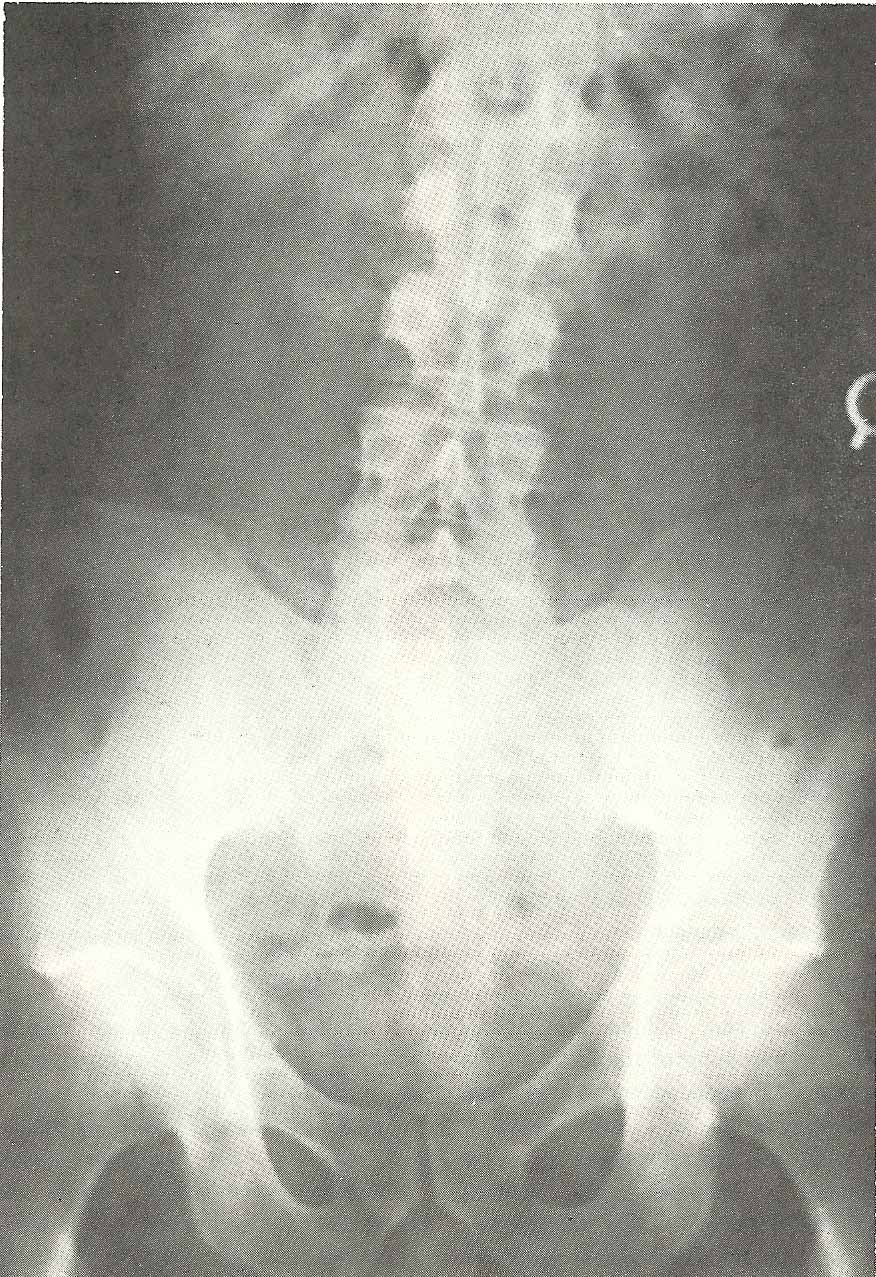

In the A-P projection (Fig. 6.31), we see a rather severe right

inclination of the vertebrae above L5, which produces a right rotoscoliosis

extending into the thoracic spine and including the vertebrae above those

visualized in this film.  |  |   |

Extension subluxation (A-2) at L4-L5 (not shown).

Severe right lateroflexion subluxation at L4-L5 (A-3) in this case, at

least partially due to asymmetrical structural development.

Scoliosis cephalic to L4 from the L4-L5 facet asymmetry. Muscular

imbalance is also a factor in this scoliosis (C-1).

Narrow interosseous spacing at L5-S1 (A-8). Discopathy is the cause of the narrowed spacing at L5-S1, and there is resultant facet arthrosis.